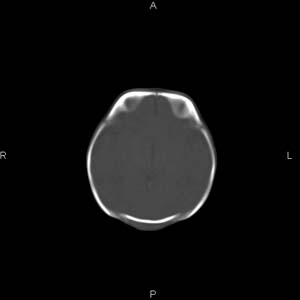

患者男,27天,出生后正常,今天中午在母亲怀里抱着吃奶在放下睡觉时发现后枕部慢慢出现一包块,来查头颅ct。无外伤史。包块内ct值47-51hu。请大家讨论。

皮下血肿,颅骨无缺如 ,颅缝无增宽。皮下血管破裂所因起。

头皮下血肿,局部枕骨略有凹陷

枕部皮下血肿 局部枕骨凹陷

颅骨无缺损,骨缝无增宽.支持头皮血肿(血管破裂)